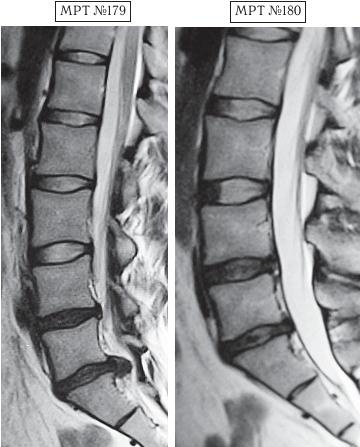

На МРТ № 183 наблюдается состояние поясничного отдела позвоночника — начальная стадия развития остеохондроза практически во всех сегментах позвоночника. На МРТ № 184 того же пациента — состояние поясничного отдела позвоночника после активного укрепления мышц спины физическими упражнениями (кинезитерапии): спондилёз, грыжи Шморля в сегментах ТXII—LI, LI—LII, LII—LIII, практически полное отсутствие межпозвонкового диска в сегменте L–Lu, значительное снижение высоты межпозвонковых дисков в сегментах LII—LIII, LIII—LIV, исправление физиологического лордоза, стеноз спинномозгового канала. Кроме того, помимо всего вышеперечисленного у пациента на уровне поражённых сегментов развился спондилоартроз. |